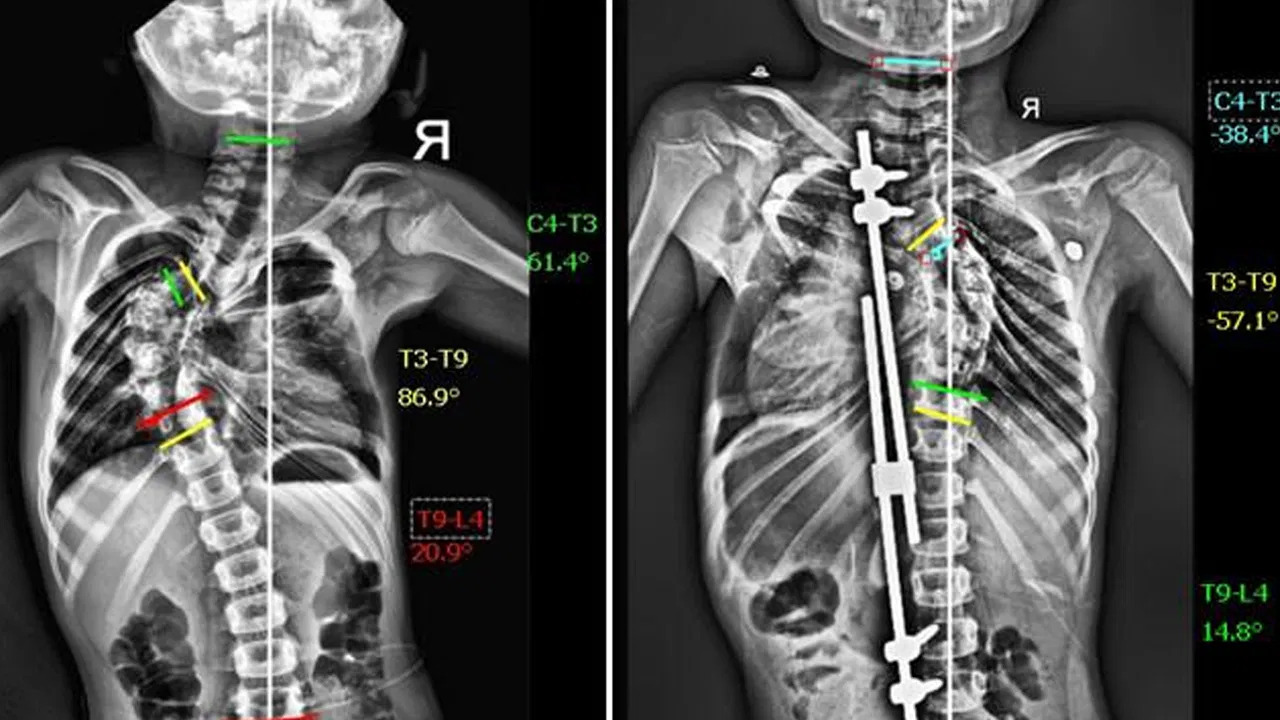

పాపకు పరీక్షలు చేయగా, ఆమె వెన్నుపూస 86 డిగ్రీల వక్రతతో ఉన్నట్లు తేలింది. ఇది “థొరాసిక్ స్కోలియోసిస్” అనే వ్యాధి, దాన్ని నిర్లక్ష్యం చేస్తే గుండె, ఊపిరితిత్తులకు సమస్యలు కలగవచ్చు. డాక్టర్ విద్యాధర రోబోటిక్ టెక్నాలజీ సాయంతో “గ్రోత్ రాడ్ సర్జరీ” చేయాలని సూచించారు. ఇది కేవలం వెన్నుపూస వక్రతను సరిచేయడం కాకుండా, అది సహజంగా పెరగడానికి కూడా సహాయపడుతుంది.